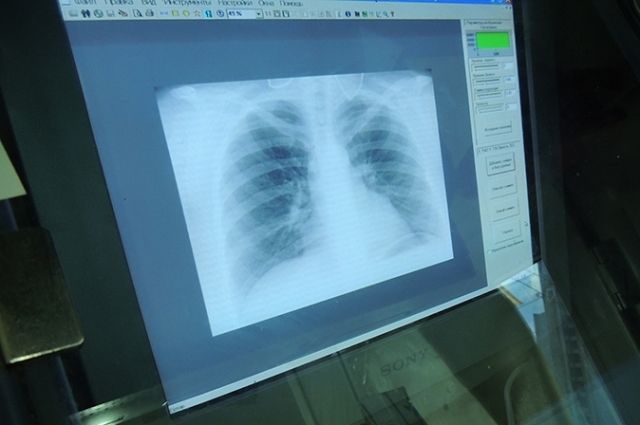

Горсовет: одесситы могут бесплатно пройти флюорографиюЕжегодно 24 марта по рекомендации Всемирной организации здравоохранения отмечается Всемирный день борьбы с туберкулезом.

В преддверии этой даты в медицинских учреждениях Одессы при поддержке Департамента здравоохранения Одесского городского совета и Одесского городского центра здоровья будет проведен День профилактики и раннего выявления заболевания туберкулезом.

В пятницу, 22 марта 2024 года, медики приглашают всех желающих пройти бесплатное профилактическое флюорографическое обследование по адресам: